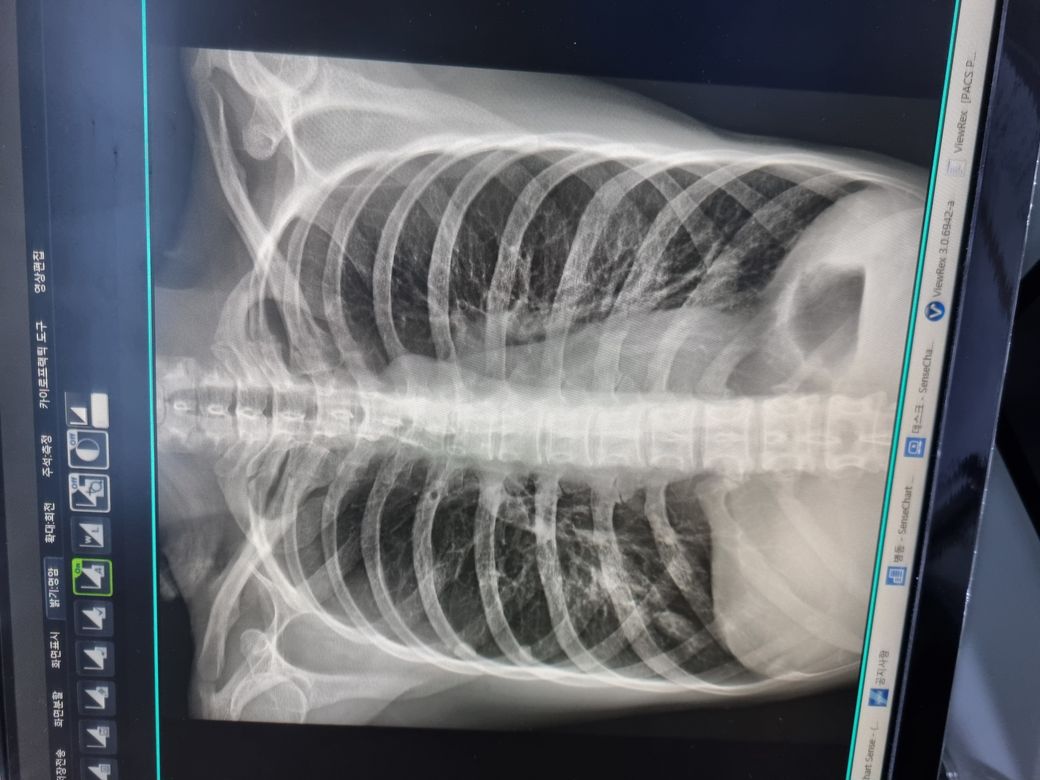

코로나 확진 6일차에 오른쪽 가슴이 콕콕 찌르는 통증 지속되어 작은 의원에서 엑스레이 찍은 사진입니다.

폐렴 의심되는 애매한 부분 있지만

흉통은 있으나 발열,기침,가래등이 없어서

경과관찰소견을 들었습니다.

아래는 3일 전 사진입니다.

3일 후인 오늘 여전히 오른쪽 가슴이 콕콕 찌르고 찝찝해서 3일만에 큰 병원 호흡기내과에서 엑스레이를 여러장 촬영했는데 이상이 없다합니다. 3일전 찍은 사진을 교수님께보여드리니 "확실히 폐렴소견이 있엇네요 오늘 사진은 괜찮습니다" 하십니다

엑스레이 장비의 성능 차이, 검사 당시의 세팅 차이 등에 의해서 폐 사진의 질 차이가 다소 있을 수 있습니다. 올리신 사진의 소견으로 보았을 대에는 우하엽 부위에 다소 음영이 증가된 소견이 있어 보입니다만 반드시 폐렴이다라고 단언할 정도까지는 아닙니다. 3일 뒤에 확인한 엑스레이 소견이 괜찮다면 우선은 약물을 복용하며 경과를 지켜보시길 권고드립니다.